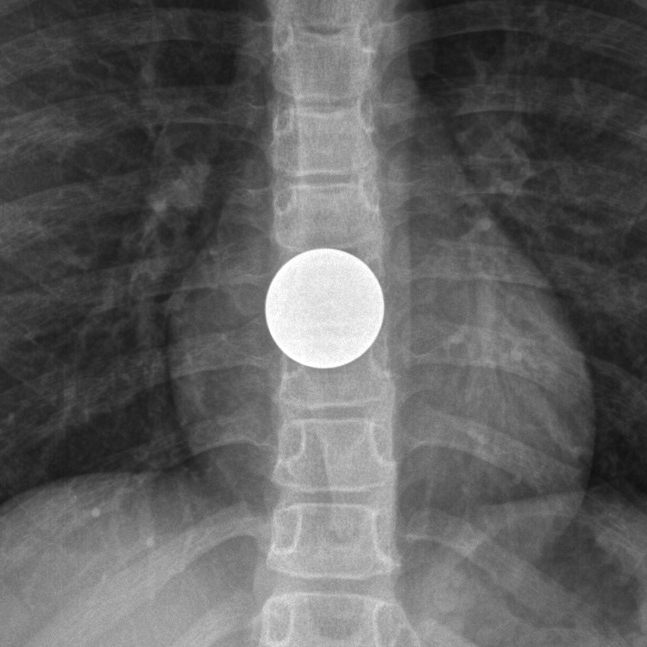

Coin Vs Battery Radiology . Importantly, a “halo” sign distinguishes a battery from another foreign body like a coin (figure 1) and it is vital that healthcare professionals recog. Hydroxide radicals produced by the button battery lodged in the esophagus can cause caustic injury, necrosis, perforation, fistula and strictures in the esophagus. Ingestion of foreign body is a common problem in children and it is important to differentiate between button battery and coin ingestion. This is because of the difference in terms of.

This is because of the difference in terms of. Ingestion of foreign body is a common problem in children and it is important to differentiate between button battery and coin ingestion. Hydroxide radicals produced by the button battery lodged in the esophagus can cause caustic injury, necrosis, perforation, fistula and strictures in the esophagus. Importantly, a “halo” sign distinguishes a battery from another foreign body like a coin (figure 1) and it is vital that healthcare professionals recog.

Coin Vs Battery Radiology This is because of the difference in terms of. Ingestion of foreign body is a common problem in children and it is important to differentiate between button battery and coin ingestion. Importantly, a “halo” sign distinguishes a battery from another foreign body like a coin (figure 1) and it is vital that healthcare professionals recog. Hydroxide radicals produced by the button battery lodged in the esophagus can cause caustic injury, necrosis, perforation, fistula and strictures in the esophagus. This is because of the difference in terms of.

Button Battery Ingestion Core EM Coin Vs Battery Radiology Ingestion of foreign body is a common problem in children and it is important to differentiate between button battery and coin ingestion. Hydroxide radicals produced by the button battery lodged in the esophagus can cause caustic injury, necrosis, perforation, fistula and strictures in the esophagus. This is because of the difference in terms of. Importantly, a “halo” sign distinguishes a. Coin Vs Battery Radiology.

Ingested button battery Image Coin Vs Battery Radiology Ingestion of foreign body is a common problem in children and it is important to differentiate between button battery and coin ingestion. Importantly, a “halo” sign distinguishes a battery from another foreign body like a coin (figure 1) and it is vital that healthcare professionals recog. Hydroxide radicals produced by the button battery lodged in the esophagus can cause caustic. Coin Vs Battery Radiology.

The apperence of the battery in the chest Xray Download Scientific Coin Vs Battery Radiology Importantly, a “halo” sign distinguishes a battery from another foreign body like a coin (figure 1) and it is vital that healthcare professionals recog. Hydroxide radicals produced by the button battery lodged in the esophagus can cause caustic injury, necrosis, perforation, fistula and strictures in the esophagus. This is because of the difference in terms of. Ingestion of foreign body. Coin Vs Battery Radiology.